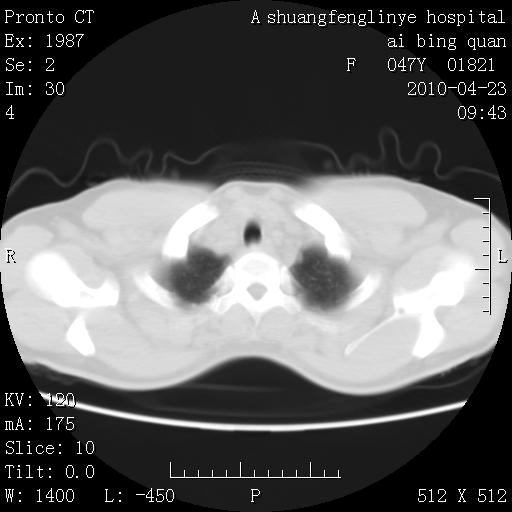

标题: CT25944:胸痛、气短、前几日高烧!肺Ca?请会诊! [打印本页]

标题: CT25944:胸痛、气短、前几日高烧!肺Ca?请会诊!

双肺多发结节,考虑转移瘤,肺癌肺转移不除外

左侧乳腺低密度灶

双肺多发结节,部分密度较高,最大结节边缘光滑。临床有“胸痛、气短、前几日高烧”病史。首选考虑:右肺感染性病变!建议积极消炎后复查!